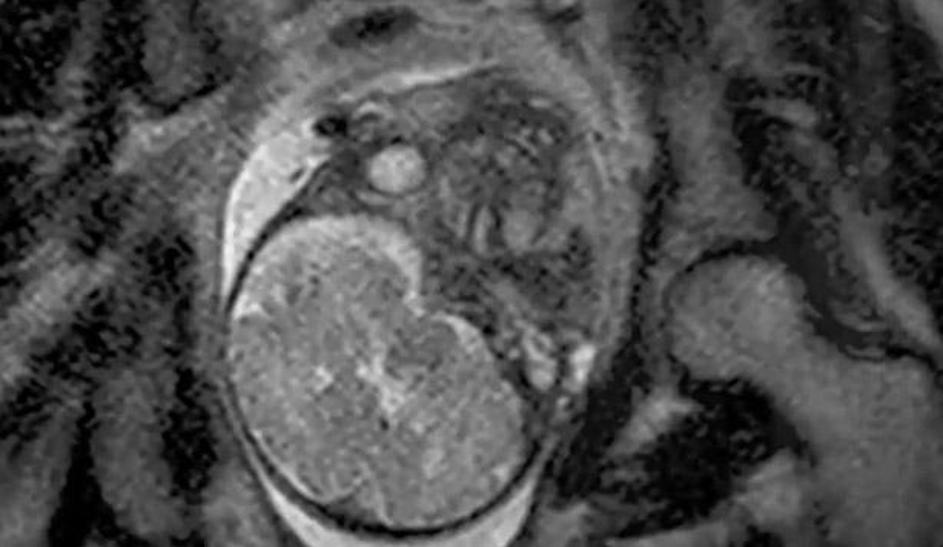

porod, snemanje, magnetna resonanca Poporodni pogled v notranjost maternice s placento. Žurnal24 porod, snemanje, magnetna resonanca